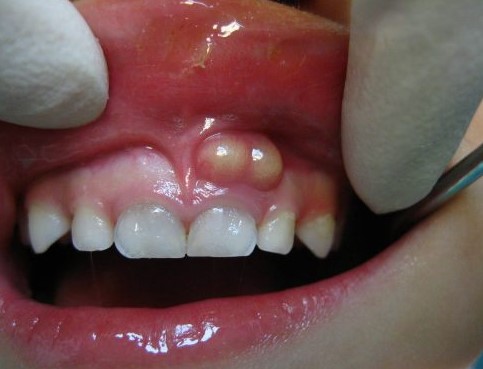

Abscess quanh chóp răng

Có thể vùng nướu ở răng bị sâu hoặc chấn thương có nốt nổi lên như mụn, ấn vào thấy có dịch hoặc mủ vàng chảy ra. Bạn hoàn toàn không thấy đau răng.

Sưng mặt, sưng lợi hay có nốt mụn ở lợi là dấu hiệu cho thấy vùng chóp răng đã bị nhiễm trùng do tủy răng chết mà không được chữa trị kịp thời. Lúc này nếu có chụp film răng, nha sĩ sẽ chỉ cho bạn thấy có vùng nhiễm trùng ở chóp răng. Vùng nhiễm trùng có thể chỉ ở tại chỗ hoặc đã lan rộng ra xung quanh.